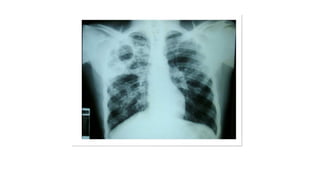

Miliary pattern

Intersticial Randomic micronodular distribution